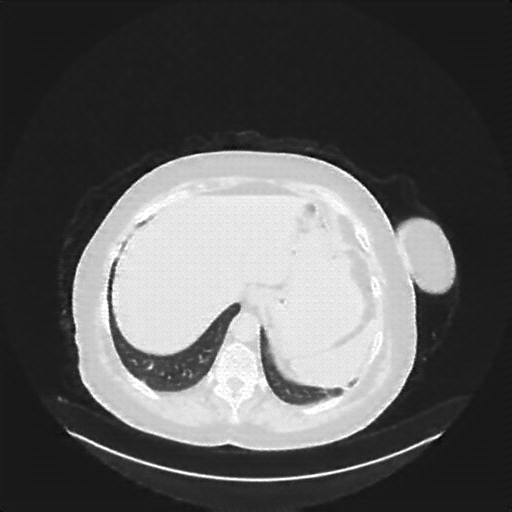

Generated VENOUS CT scan (A→B translation)

Full window (WL 1023.5, WW 4095 β†’ Low βˆ’1024, High +3071)

Lung window (WL -600, WW 1500 β†’ Low βˆ’1350, High +150)